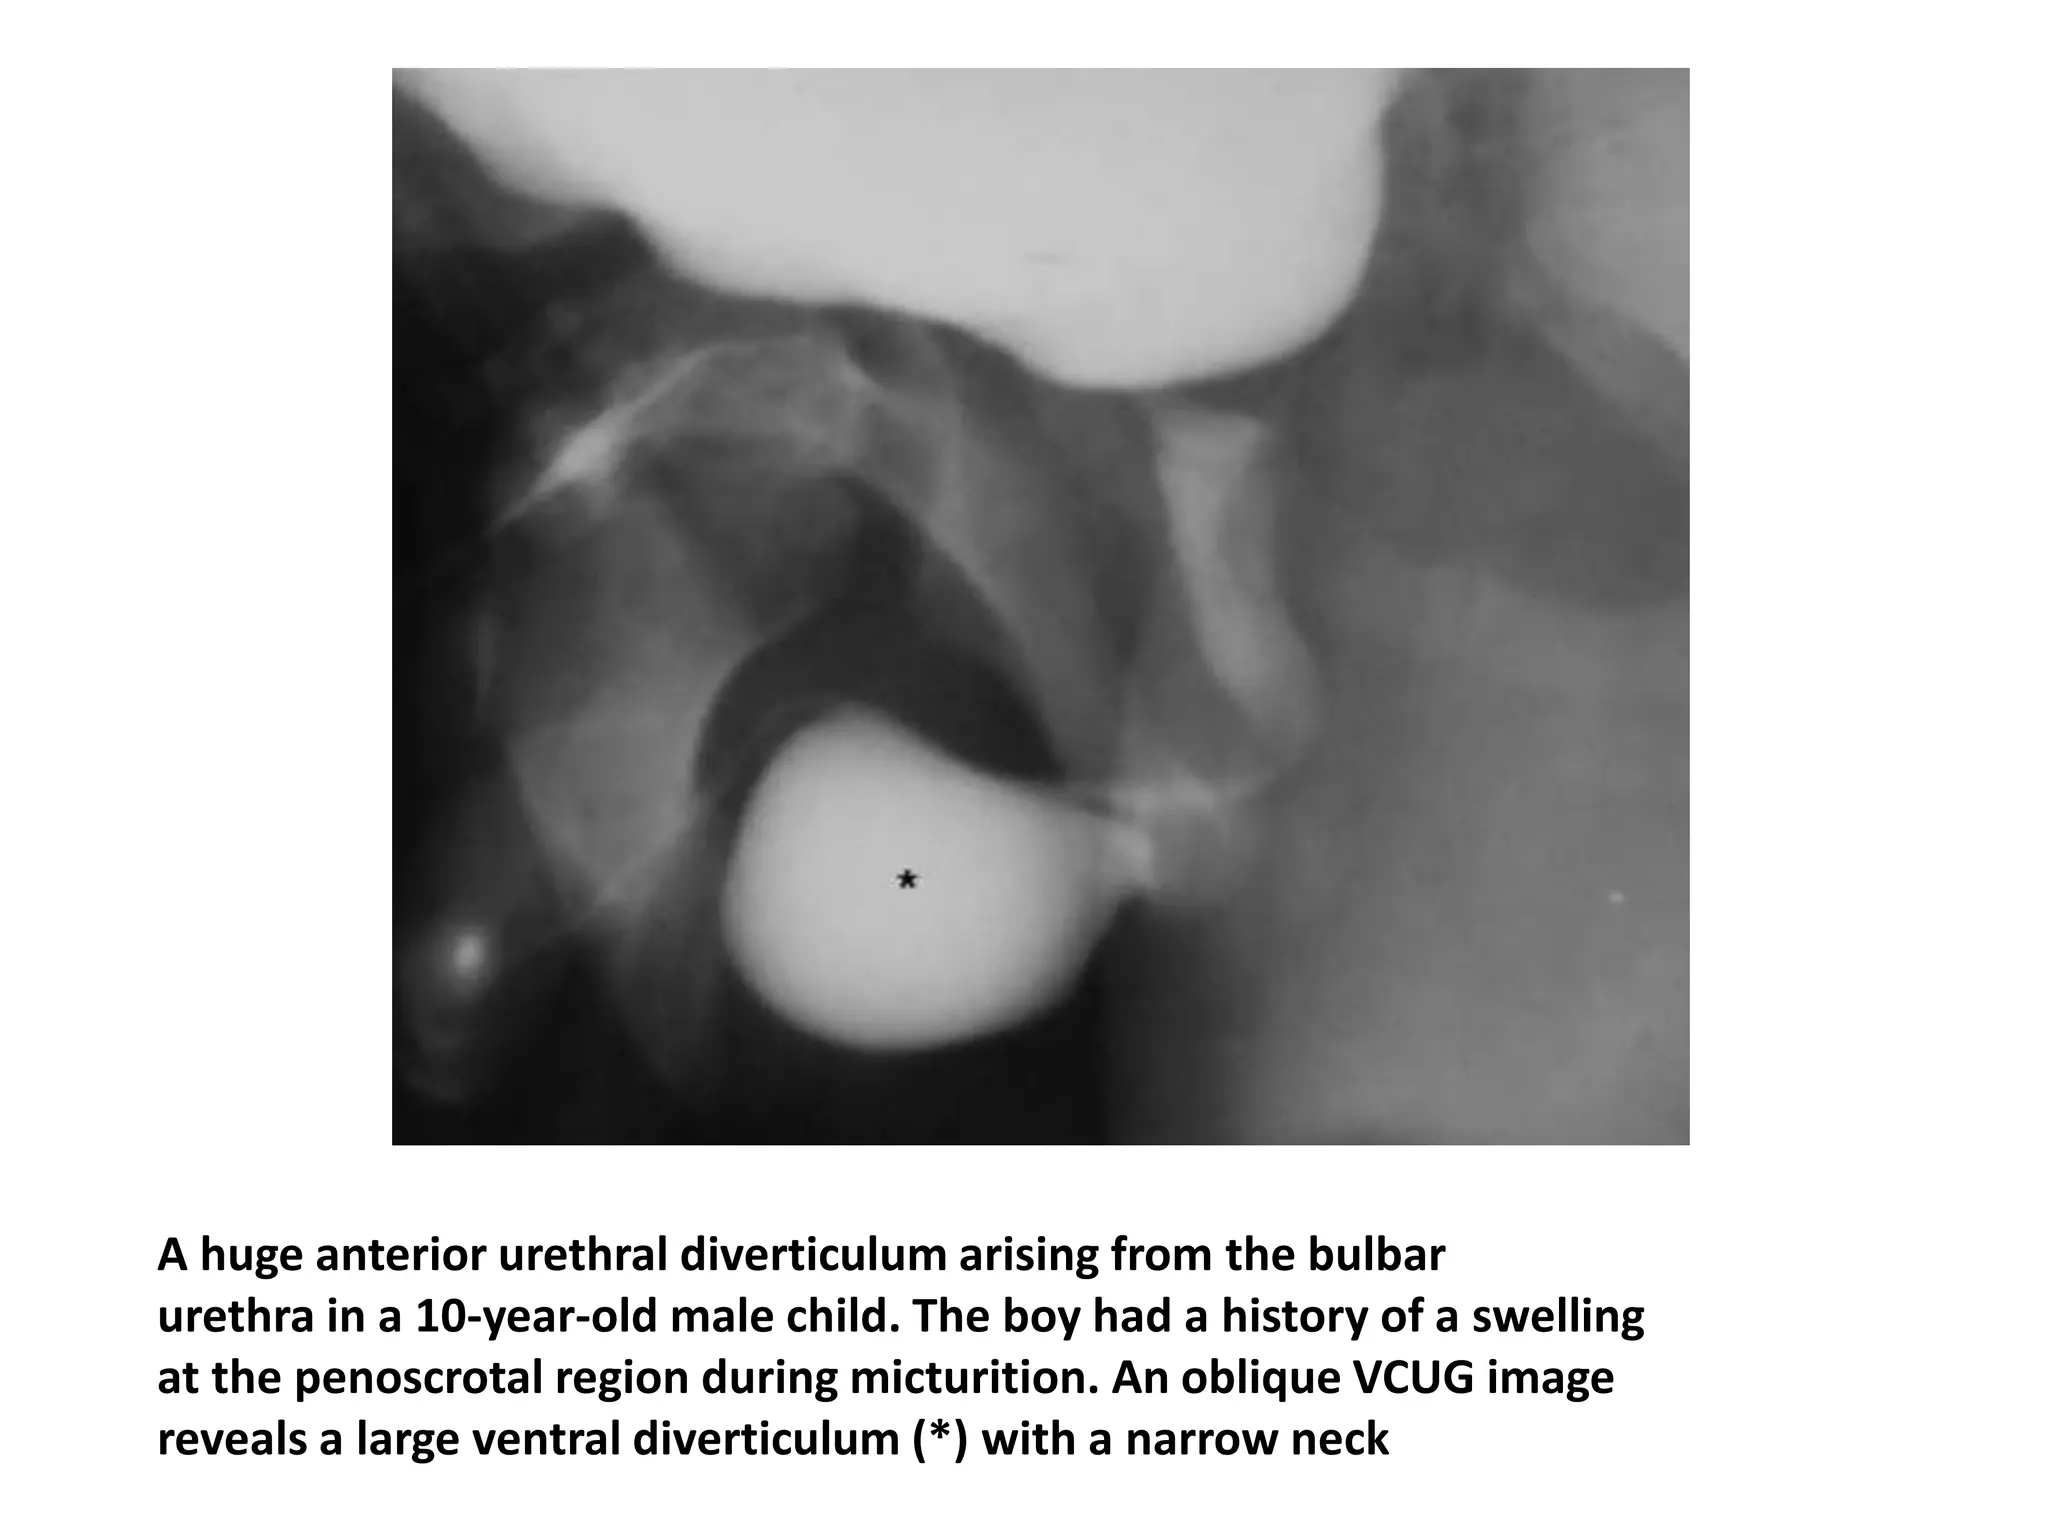

A huge anterior urethral diverticulum arising from the bulbar

urethra in a 10-year-old male child. The boy had a history of a swelling

at the penoscrotal region during micturition. An oblique VCUG image

reveals a large ventral diverticulum (*) with a narrow neck